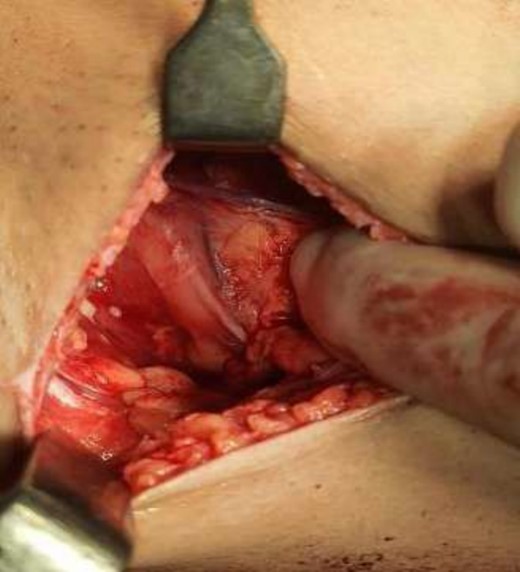

The operating surgeon opted for a vertical mastopexy to remove the mass and simultaneously reconstruct the breast to restore it as much as possible and to have a cosmetically better scar (Fig. 7). The skin was marked, a peri-areolar ellipse having a diameter of about 15 cm was made that extended vertically below, 4 cm above the inframammary fold. The skin was dissected along the incision line and the mass was removed. Grossly, the specimen measuring 5 × 3.5 × 3 cm3, containing the firm mass, was sent for histopathological analysis. Axillary lymph node biopsy was done. Two drains were placed, and the skin was closed in the form of a superior circle and an inferior ellipse (Figs 3–6).

The frozen section diagnosis revealed secretory carcinoma, unifocal, 2.3 × 1.7 × 1.5 cm3 in size. Skin was unremarkable and free of tumor. There was no intraductal component. All the resection margins were free of tumor and the closest superior margin was free by less than 0.1 cm. A total of 16 lymph nodes were isolated from axillary tissue, all of which were negative for metastatic carcinoma (0/16). No venous, lymphatic or perineural invasion was identified. Pathological staging revealed primary tumor; pT2, lymph nodes; pN0, distant metastasis; pMx. Estrogen and progesterone receptors were negative (Fig. 8).

Mastectomy along with sentinel lymph node biopsy procedure (Tumor extracted).